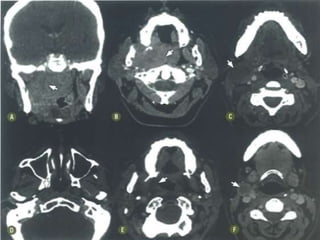

 TC contrastada é o método de escolha (1-3 mm).

 RM  T1, T2, STIR, gadolíneo, supressão de

gordura, difusão.

Nasofaringe  TC contrastadaé o método de escolha (1-3 mm).  RM  T1, T2, STIR, gadolíneo, supressão de gordura, difusão.